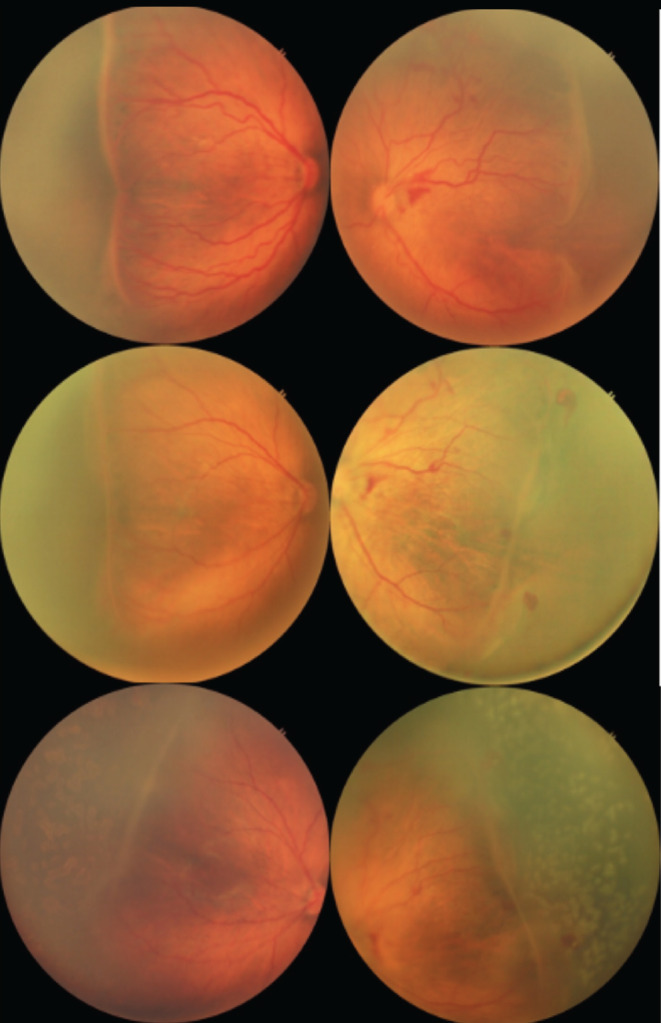

Materials and methods: This study evaluated disease regression and rescue therapy requirement in treatment-naïve ROP cases treated with IVR. Among 188 screened patients, 80 had ROP. Thirty-eight patients (76 eyes) with type 1 ROP and aggressive ROP (AROP) were included. Treatment involved a single dose of 0.2 mg ranibizumab injected under aseptic conditions. Patients were monitored post-treatment for up to 6 months. Recurrence of disease was managed with argon laser photocoagulation targeting the peripheral avascular retina. Data analysis utilized t-tests for continuous variables and χ² tests for categorical data, with a significance threshold of p<0.05.

Results: The study included 19 males and 19 females, with 56 eyes having AROP and 20 eyes with type 1 ROP. All AROP cases required rescue therapy, with a mean interval of 3.43±0.84 weeks between treatments. Sixty percent of type 1 ROP eyes also needed laser therapy. While type 1 ROP cases had slightly higher gestational age and lower birth weight compared to AROP, these differences were not statistically significant (p=0.081 and p=0.27, respectively). However, the interval between treatments was significantly longer in type 1 ROP than in AROP (p=0.0016).

Conclusion: Ranibizumab demonstrated effectiveness in initial disease regression but was linked to reactivation in all AROP and 60% of type 1 ROP cases, highlighting the importance of more frequent follow-ups after ranibizumab injection, particularly for AROP patients.